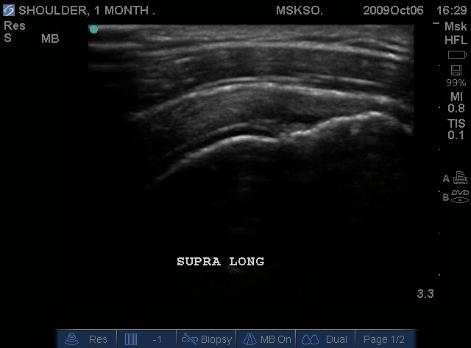

Anterior movement of the probe from the prior image shows beginning of cortical irregularities seen at the lateral Greater Tuberosity

Anterior Greater Tuberosity imaged as a more pronounced curved cortical margin. This area of the insertion is truly Supraspinatus with no Infraspinatus merger. Here we see more cortical irregularity deeper into the cortex.